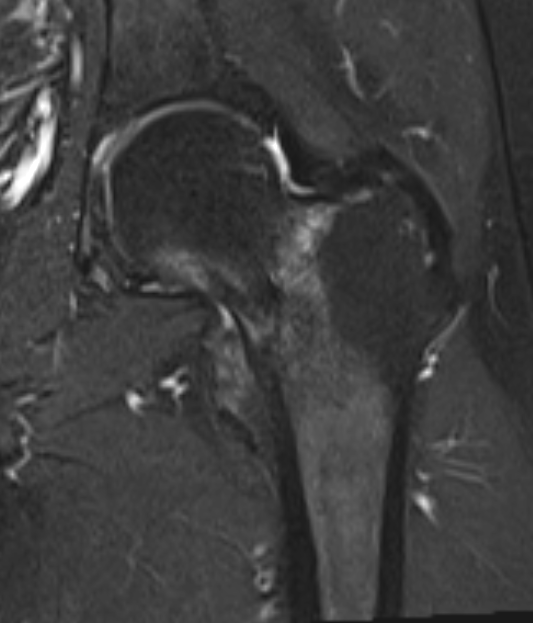

Edema / fracture line / hip effusion

MRI demonstrating edema likely across entire neck

MRI demonstrates complete fracture